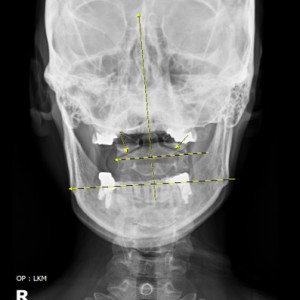

안면 두개골 엑스레이 검사

Submento Vertex View 포함

안면 균형검사

턱의 다양한 각도 사진 촬영